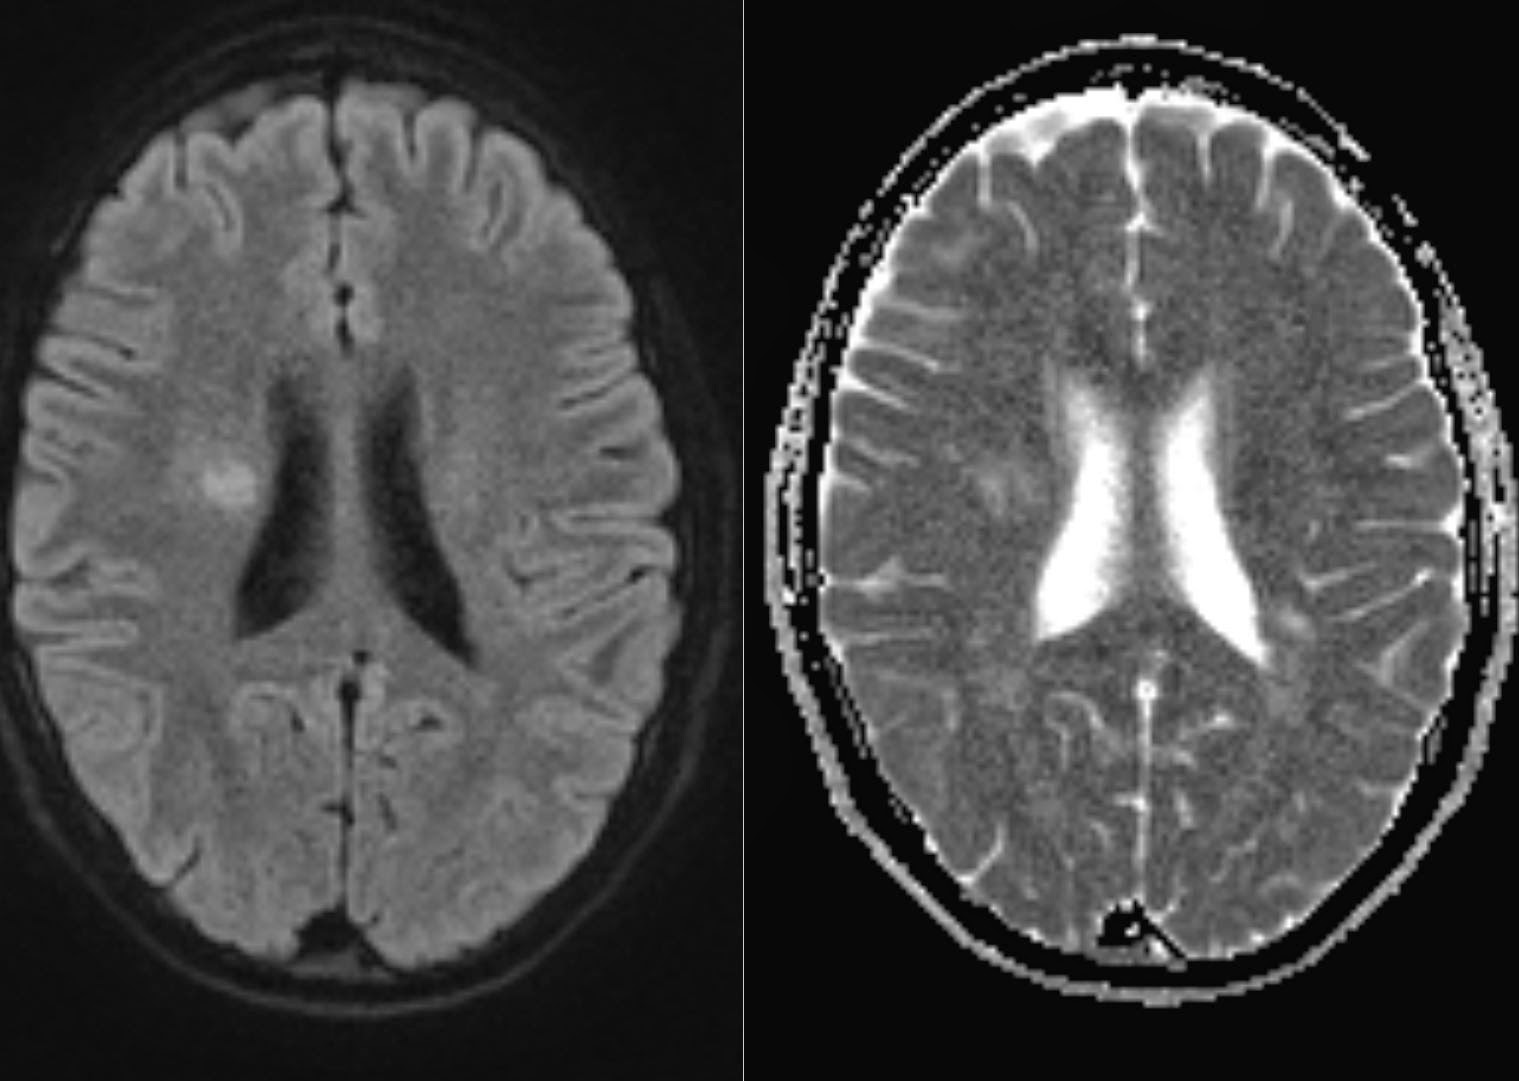

From radiologykey.com

Diffusion Resonance Imaging in Multiple Sclerosis Radiology Key Plaque In Brain On Mri Mri, or magnetic resonance imaging, reveals these. while experts may not be able to confirm cerebral amyloid angiopathy before death, they can still make a highly probable. white spots on your mri can show up even if you have no symptoms of illness. white matter disease refers to changes in the brain's white matter, the part of. Plaque In Brain On Mri.

From radiologymri.blogspot.com

Radiology MRI Active MS plaques on DWI b1000 Plaque In Brain On Mri — mayo clinic researchers led a laboratory study that found a new way to prevent the accumulation of amyloid. Mri, or magnetic resonance imaging, reveals these. these appear as bright areas or white matter ‘hyperintensities’ on some brain mri scans. while experts may not be able to confirm cerebral amyloid angiopathy before death, they can still make a. Plaque In Brain On Mri.